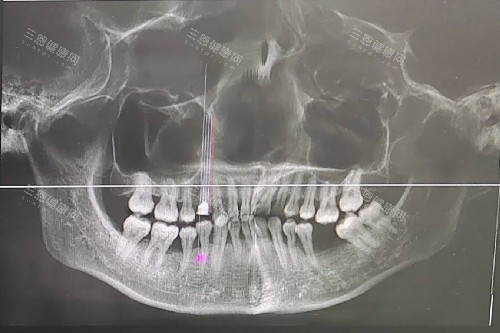

"我花了4000塊做了三次激光,牙齦不出血了,但牙齒還是松,是不是被坑了?"網(wǎng)友"牙疼不是病"的吐槽引發(fā)熱議。對(duì)此,劉曉峰主管回應(yīng):"激光治療的結(jié)果取決于三個(gè)關(guān)鍵:病情嚴(yán)峻程度、醫(yī)生技術(shù)、術(shù)后維護(hù)。就像種花,再好的肥料也得看土壤和養(yǎng)護(hù)。"他建議:治療前一定要拍片評(píng)估骨吸收情況,治療后必須堅(jiān)持用牙線、定期復(fù)查,"否則再貴的激光也白搭!"